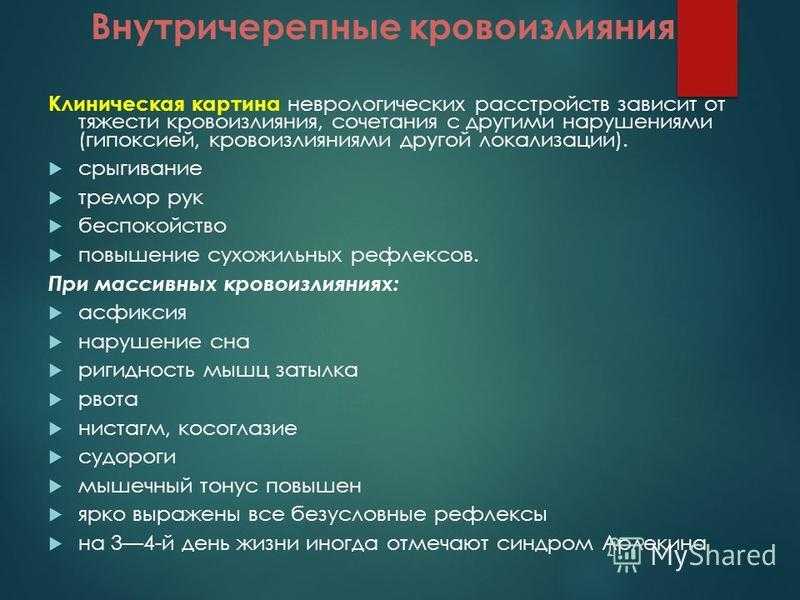

Внутричерепные кровоизлияния у новорожденных презентация - 92 фото